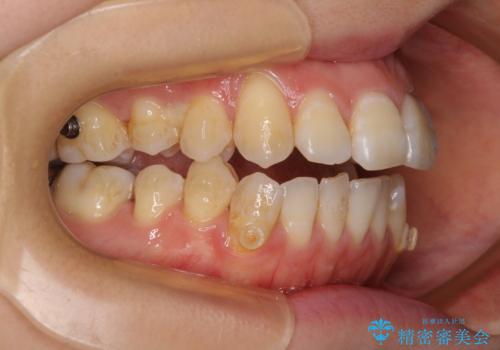

八重歯と開咬の抜歯矯正 ワイヤー装置を併用したインビザライン矯正治療

- 咬み合わない前歯と八重歯などのデコボコを気にして来院された患者様です。

上下前歯の位置を比較すると上顎が前方にあり、デコボコ改善でより上顎が前方に行く可能性があります。

開咬の改善にはインビザラインが有効であり、インビザライン単体での治療を検討しましたが、上顎前突を回避するために上顎左側第一小臼歯抜歯を行うこととしたため、補助装置とワイヤー矯正を併用した上で、インビザラインによる矯正治療を行うこととしました。